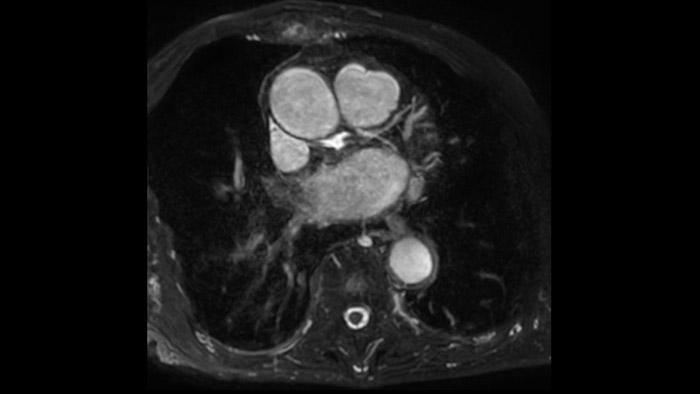

Diagnostic and prognostic utility of cardiac MR is increasing. Assess the anatomy and function of the heart using cine acquisitions, acquire information about perfusion and viability of the cardiac tissue, visualise potential edema with black blood sequence, access and even quantify tissue characterisation with CardiacQuant.

IntelliSpace Portal MR Caas5,6 4D Flow post-processing solution enables generation of 3D volume reconstructions, to visualise and evaluate blood flow in cardiovascular structures, including heart valves, chambers, and vessels, based on cardiovascular MR 4D Flow imaging.